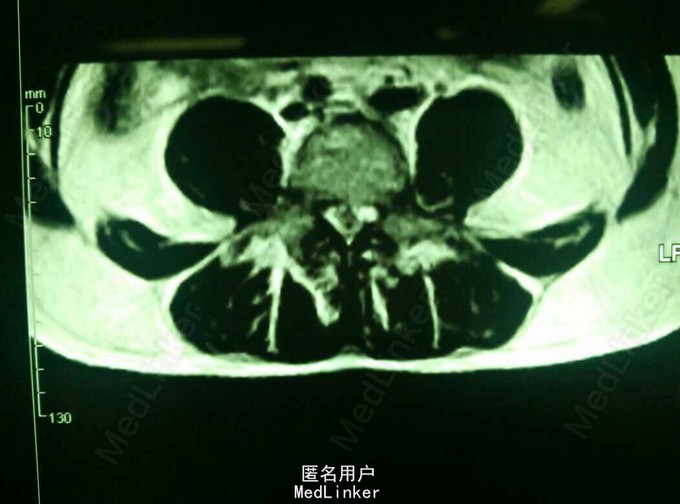

患者,男,45岁,因“腰痛伴右下肢放射痛1月,加重3天”入院。既往身体健康。

查体:脊柱无畸形,腰部L5S1间隙处轻压痛,脊柱无叩击痛,右小腿外侧及足底触痛觉减退,右下肢肌力4级,右下肢直腿抬高试验40度。 MRI提示:L5S1椎间盘脱出,髓核游离要椎管。